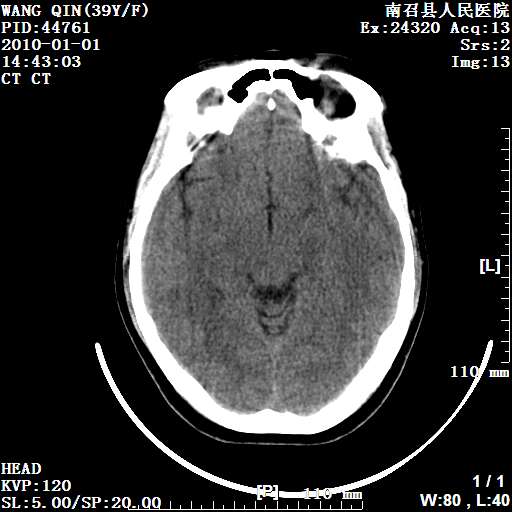

以下是引用随光逐影在2010-1-22 9:03:00的发言:[br]考虑左侧中颅窝(蝶骨翼区)脑膜瘤侵犯蝶骨翼并突入左侧眼眶。

以下是引用水过无痕在2010-1-22 14:55:00的发言:[br]一、定位:颅外占位;二、定性:恶性可能性大;三、组织来源:来源于左侧眼外直肌或其他部位;考虑为:横纹肌肉瘤>转移瘤>脑膜瘤.